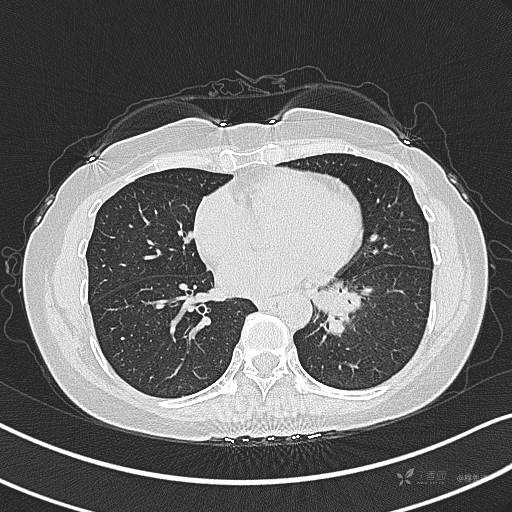

CT平扫

肺窗